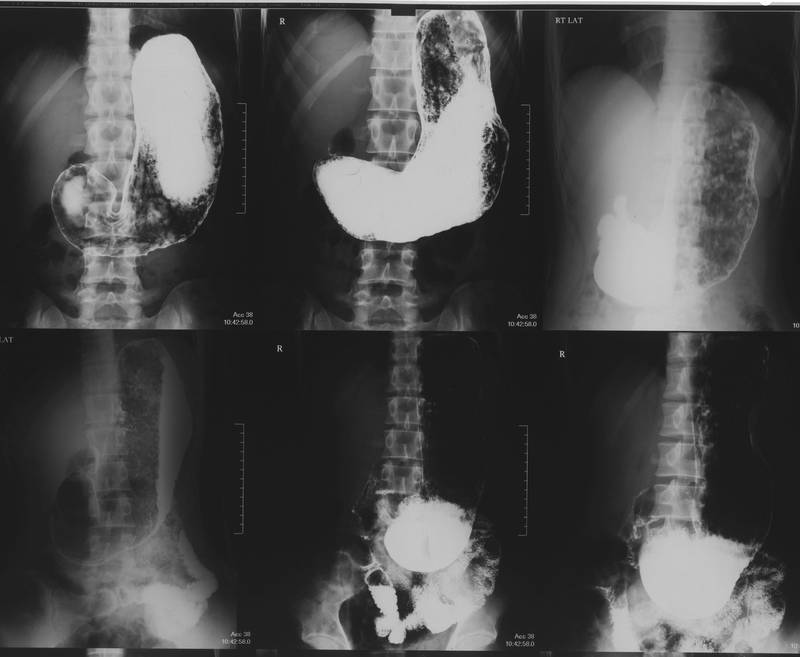

Фото 39 — Гастроэнтероскопия для исследования ЖКТ